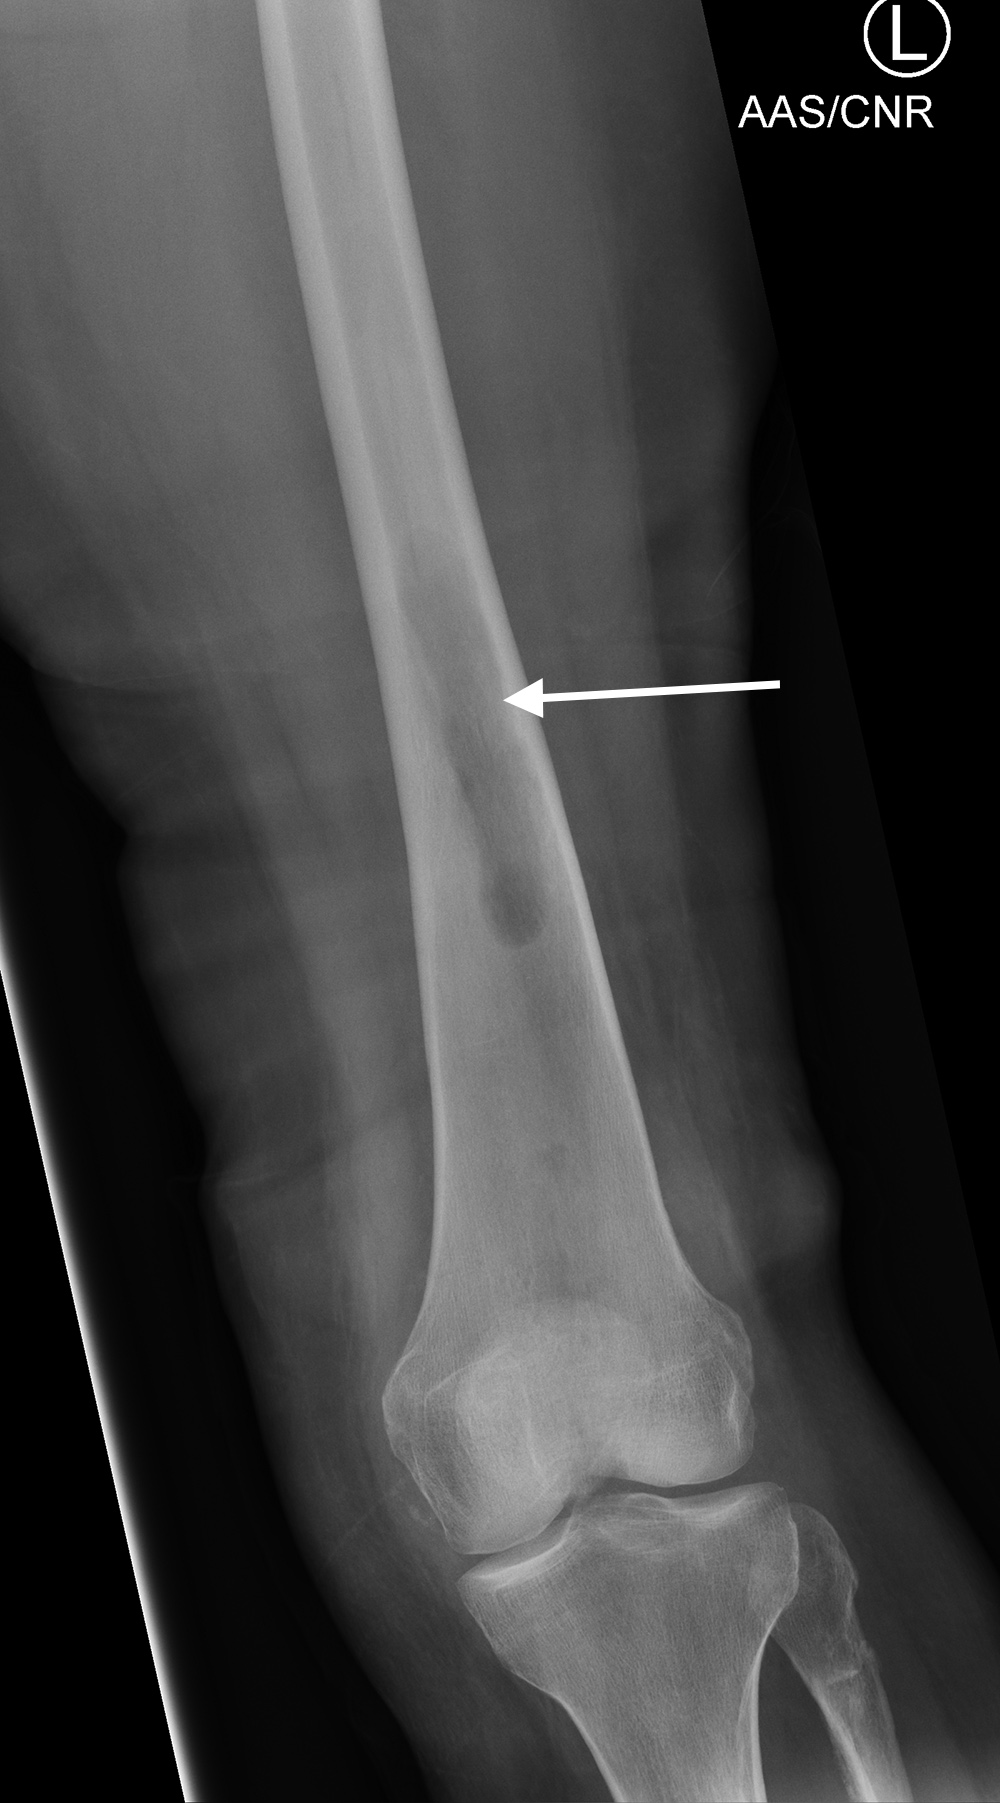

Ultrasonic bone stimulator AP view Ultrasonic bone stimulator lateral view

71-year old woman with left proximal tibia and fibula fractures with delayed healing. A bone stimulator was placed to enhance bony healing. Courtesy Kellon Hansen, MD.